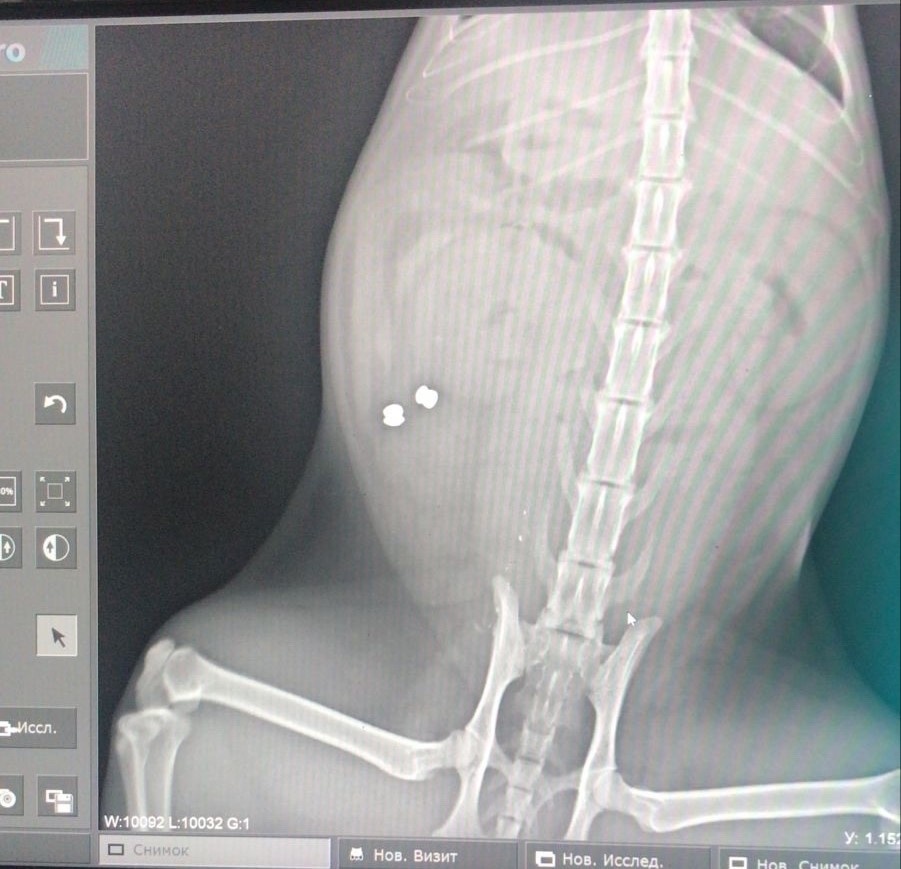

На фото вы видите рентгеновский снимок кота, в которого стреляли.

Пули были выпушены в область задних конечностей, а затем попали в брюшную область.